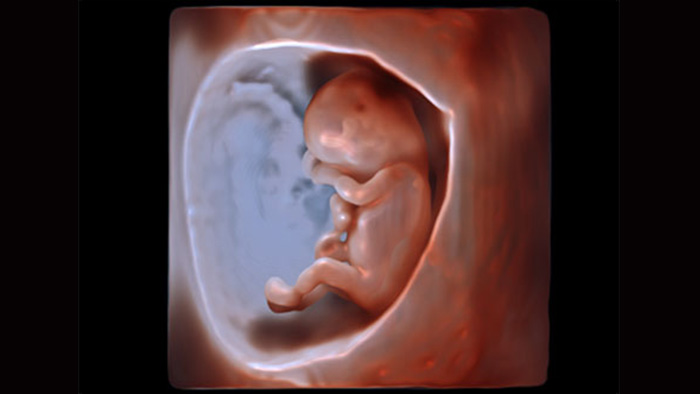

El paquete de funciones de visualización avanzada de Philips le permite obtener imágenes reales en 3D. TrueVue y GlassVue de Philips ofrecen imágenes para obstetricia y ginecología de calidad fotográfica mientras una segmentación 3D automática con aReveal le permite mostrar el rostro del feto con un solo toque.

TrueVue de Philips, con su fuente de iluminación virtual, es un método patentado de visualización avanzada de ultrasonido 3D que ofrece una asombrosa imagen de ultrasonido 3D real y permite al operador trasladar la fuente de iluminación a cualquier lugar en el volumen 3D. La flexibilidad de la fuente de iluminación permite al usuario manipular la luz y la sombra en las estructuras anatómicas para dar más seguridad al clínico, y además puede estimular el vínculo materno-fetal.

La presentación de TrueVue es más «realista» que los algoritmos de representación tradicional.

GlassVue permite ver el feto en sus etapas tempranas.

GlassVue de Philips, con una fuente de iluminación interna, ofrece una visualización temprana y más transparente de la anatomía fetal que el ultrasonido tradicional. La herramienta avanzada de imagenología 3D traspasa la superficie y permite ver los huesos, los órganos y otras estructuras internas. Los usuarios controlan la fuente de iluminación flexible y el nivel de transparencia en el volumen 3D.